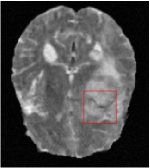

All the experiments are implemented on a Windows workstation with Intel Core i9 CPU at 3.3GHz and an Nvidia GTX-1080Ti GPU with 11GB of graphics card memory via TensorFlow Abadi et al. (2016). The parameters in the proposed network are initialized by using Xavier initialization Glorot and Bengio (2010). We trained the meta-learning network with four tasks synergistically associated with four different CS ratios: 10%, 20%, 30%, and 40%, and test the well-trained model on the testing dataset with the same masks of these four ratios. We have 300 training data for each CS ratio, which amount to total of 1200 images in the training dataset. The results for and MR reconstructions are shown in Tables 5.4 and 5.4 respectively. The associated reconstructed images are displayed in Figures 1 and 3. We also test the well-trained meta-learning model on unseen tasks with radio masks for skewed ratios: 15%, 25%, 35%, and random Cartesian masks with ratios 10%, 20%, 30% and 40%. The task-specific parameter for the unseen tasks are retrained for different masks with different sampling ratios individually with fixed task-invariant parameters . In this experiments, we only need to learn for three skewed CS ratios with radio mask and four regular CS ratios with Cartesian masks. The experimental training proceed on less data and iterations, where we performed on 100 MR images with 50 epochs. For example, for reconstructing MR images with CS ratio 15% radio mask, we fix the parameter and retrain the task-specific parameter on 100 raw data with 50 epochs, then test with renewed on our testing data set with raw measurement that sampled from radio mask with CS ratio 15%. The results associated with radio masks are shown in Table 5.4 and 5.4, Figure 2 and 4 for and images respectively. The results associated with Cartesian masks are list in Table 5.4 and reconstructed images are displayed in Figure 5.

Qualitative comparison between conventional and Meta-learning methods are shown in Figure 1 and 3, which display the reconstructed MR images of the same slice for T1 and T2 respectively, we label the zoomed-in details of HGG in the red boxes. We observe the evidence that conventional learning is more blurry and lost sharp edges, especially in lower CS ratios. From the point-wise error map, we find meta-learning has the ability to reduce noises especially in some detailed and complicated regions comparing to conventional learning.